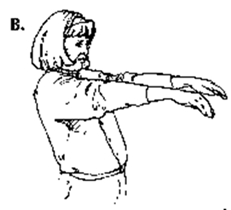

Here are some exercises intended to help prevent Carpal Tunnel Syndrome. Remember doing a quick 5 minute exercise warm up before starting work, just as runners stretch before a run, can help prevent work-related injuries.

A. Extend and stretch both wrists and fingers acutely as if they are in a hand stand position. Hold for a count of 5.

A. Extend and stretch both wrists and fingers acutely as if they are in a hand stand position. Hold for a count of 5.